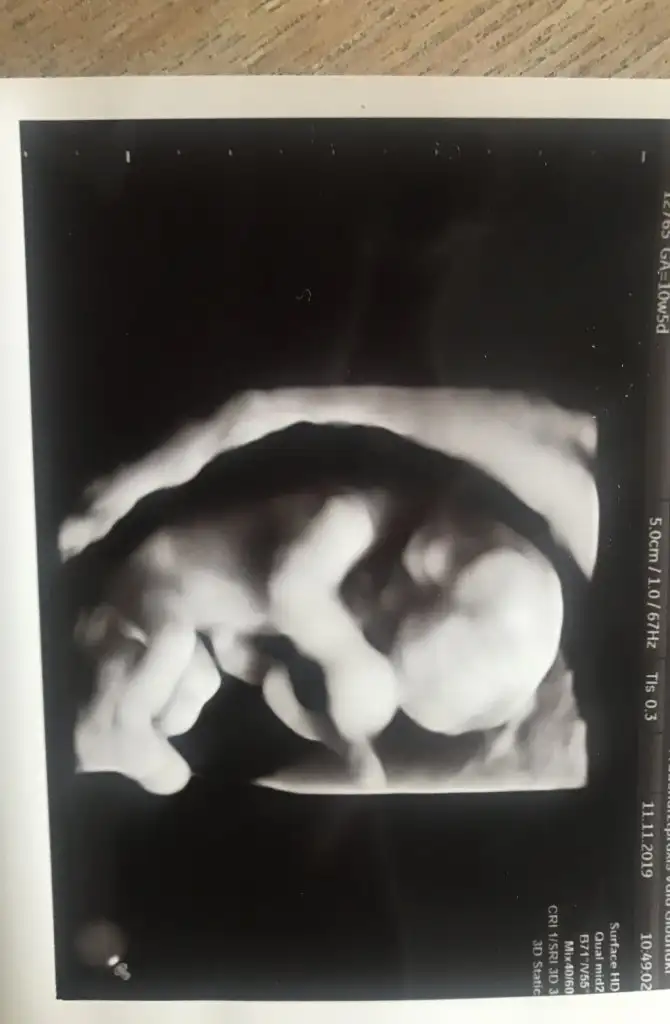

Merhaba 11 haftalık tahmin eder misiniz